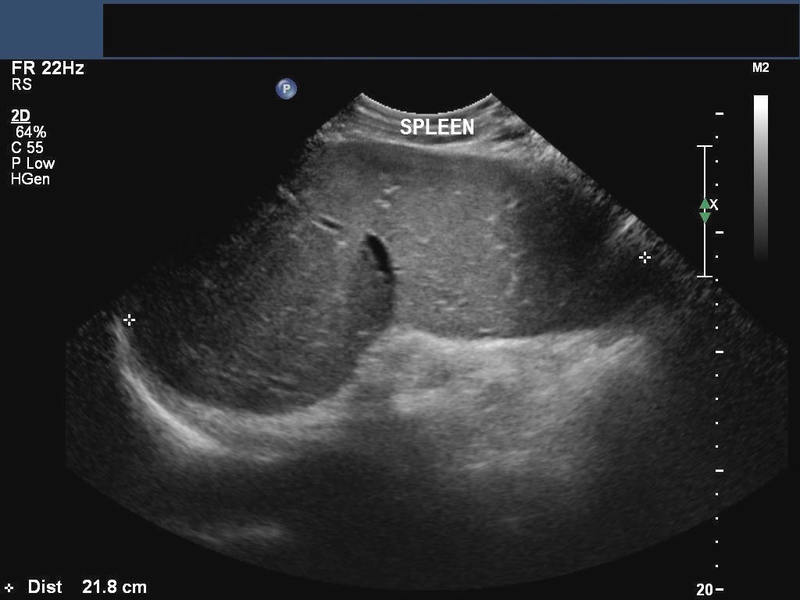

Liver/ Spleen involvement in Schistosomiasis

his patient is a known case of Bilharziasis and ultrasound showed hepatosplenomegaly with increased echogenicity of the periportal regions of the portal veins suggesting periportal fibrosis. Fibrosis of the periportal regions of the liver is a known complication of hepatic involvement in schistosomiasis. Ultrasound images are courtesy of Ravi Kadasne, MD, UAE.